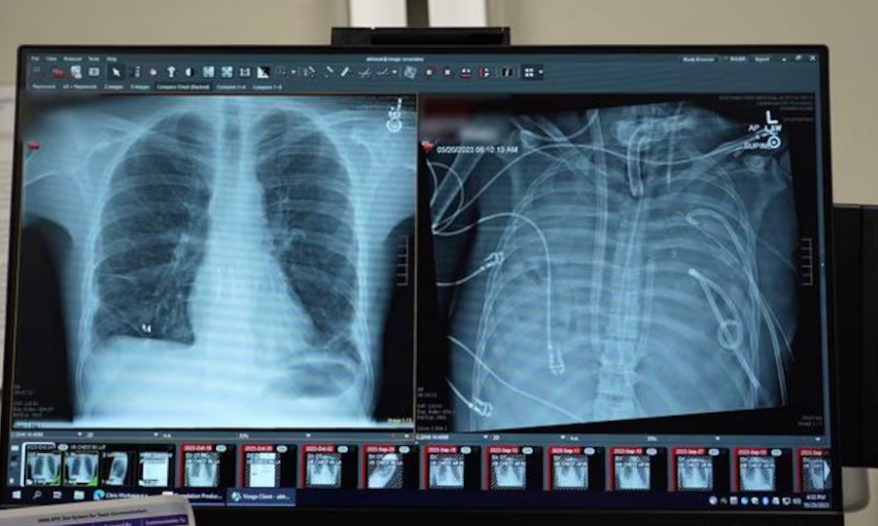

Na sala de cirurgia de um hospital de Chicago, uma equipe médica apostou tudo para salvar uma vida. Um paciente de 33 anos sobreviveu durante 48 horas sem pulmões, conectado a um sistema artificial que substituiu temporariamente a função desses órgãos, até receber um transplante duplo de pulmão.

O paciente deu entrada no hospital após contrair influenza B, que evoluiu para uma pneumonia bacteriana grave. Em seguida, desenvolveu síndrome do desconforto respiratório agudo (SDRA), condição em que os pulmões deixam de absorver oxigênio adequadamente.

O quadro se agravou ainda mais quando uma bactéria resistente, a Pseudomonas aeruginosa, infectou os pulmões, provocando falência cardíaca e renal.

Diante da situação extrema, a equipe da Northwestern Medicine adotou uma solução inédita: a remoção completa dos dois pulmões e a conexão do paciente a um sistema de pulmão artificial total, desenvolvido no próprio hospital.

A tecnologia, chamada de “sistema total de pulmão artificial extracorpóreo adaptado ao fluxo”, é capaz de oxigenar o sangue, remover o dióxido de carbono, manter a circulação sanguínea estável e preservar a função cardíaca.

Diferentemente de técnicas já conhecidas, como a oxigenação por membrana extracorpórea (ECMO), o novo sistema permite que o coração continue bombeando sangue de forma eficiente mesmo na ausência dos pulmões.

Durante 48 horas, o paciente permaneceu sem pulmões, com o tórax vazio e conectado exclusivamente ao sistema artificial. Após a melhora do quadro, ele foi incluído na lista de transplantes e, dois dias depois, passou por um transplante duplo de pulmão.

A análise dos pulmões removidos mostrou que o dano era irreversível, com cicatrizes extensas e destruição do tecido em nível molecular. Para os pesquisadores, isso representa uma evidência biológica de que alguns casos de SDRA não têm possibilidade de recuperação sem transplante.